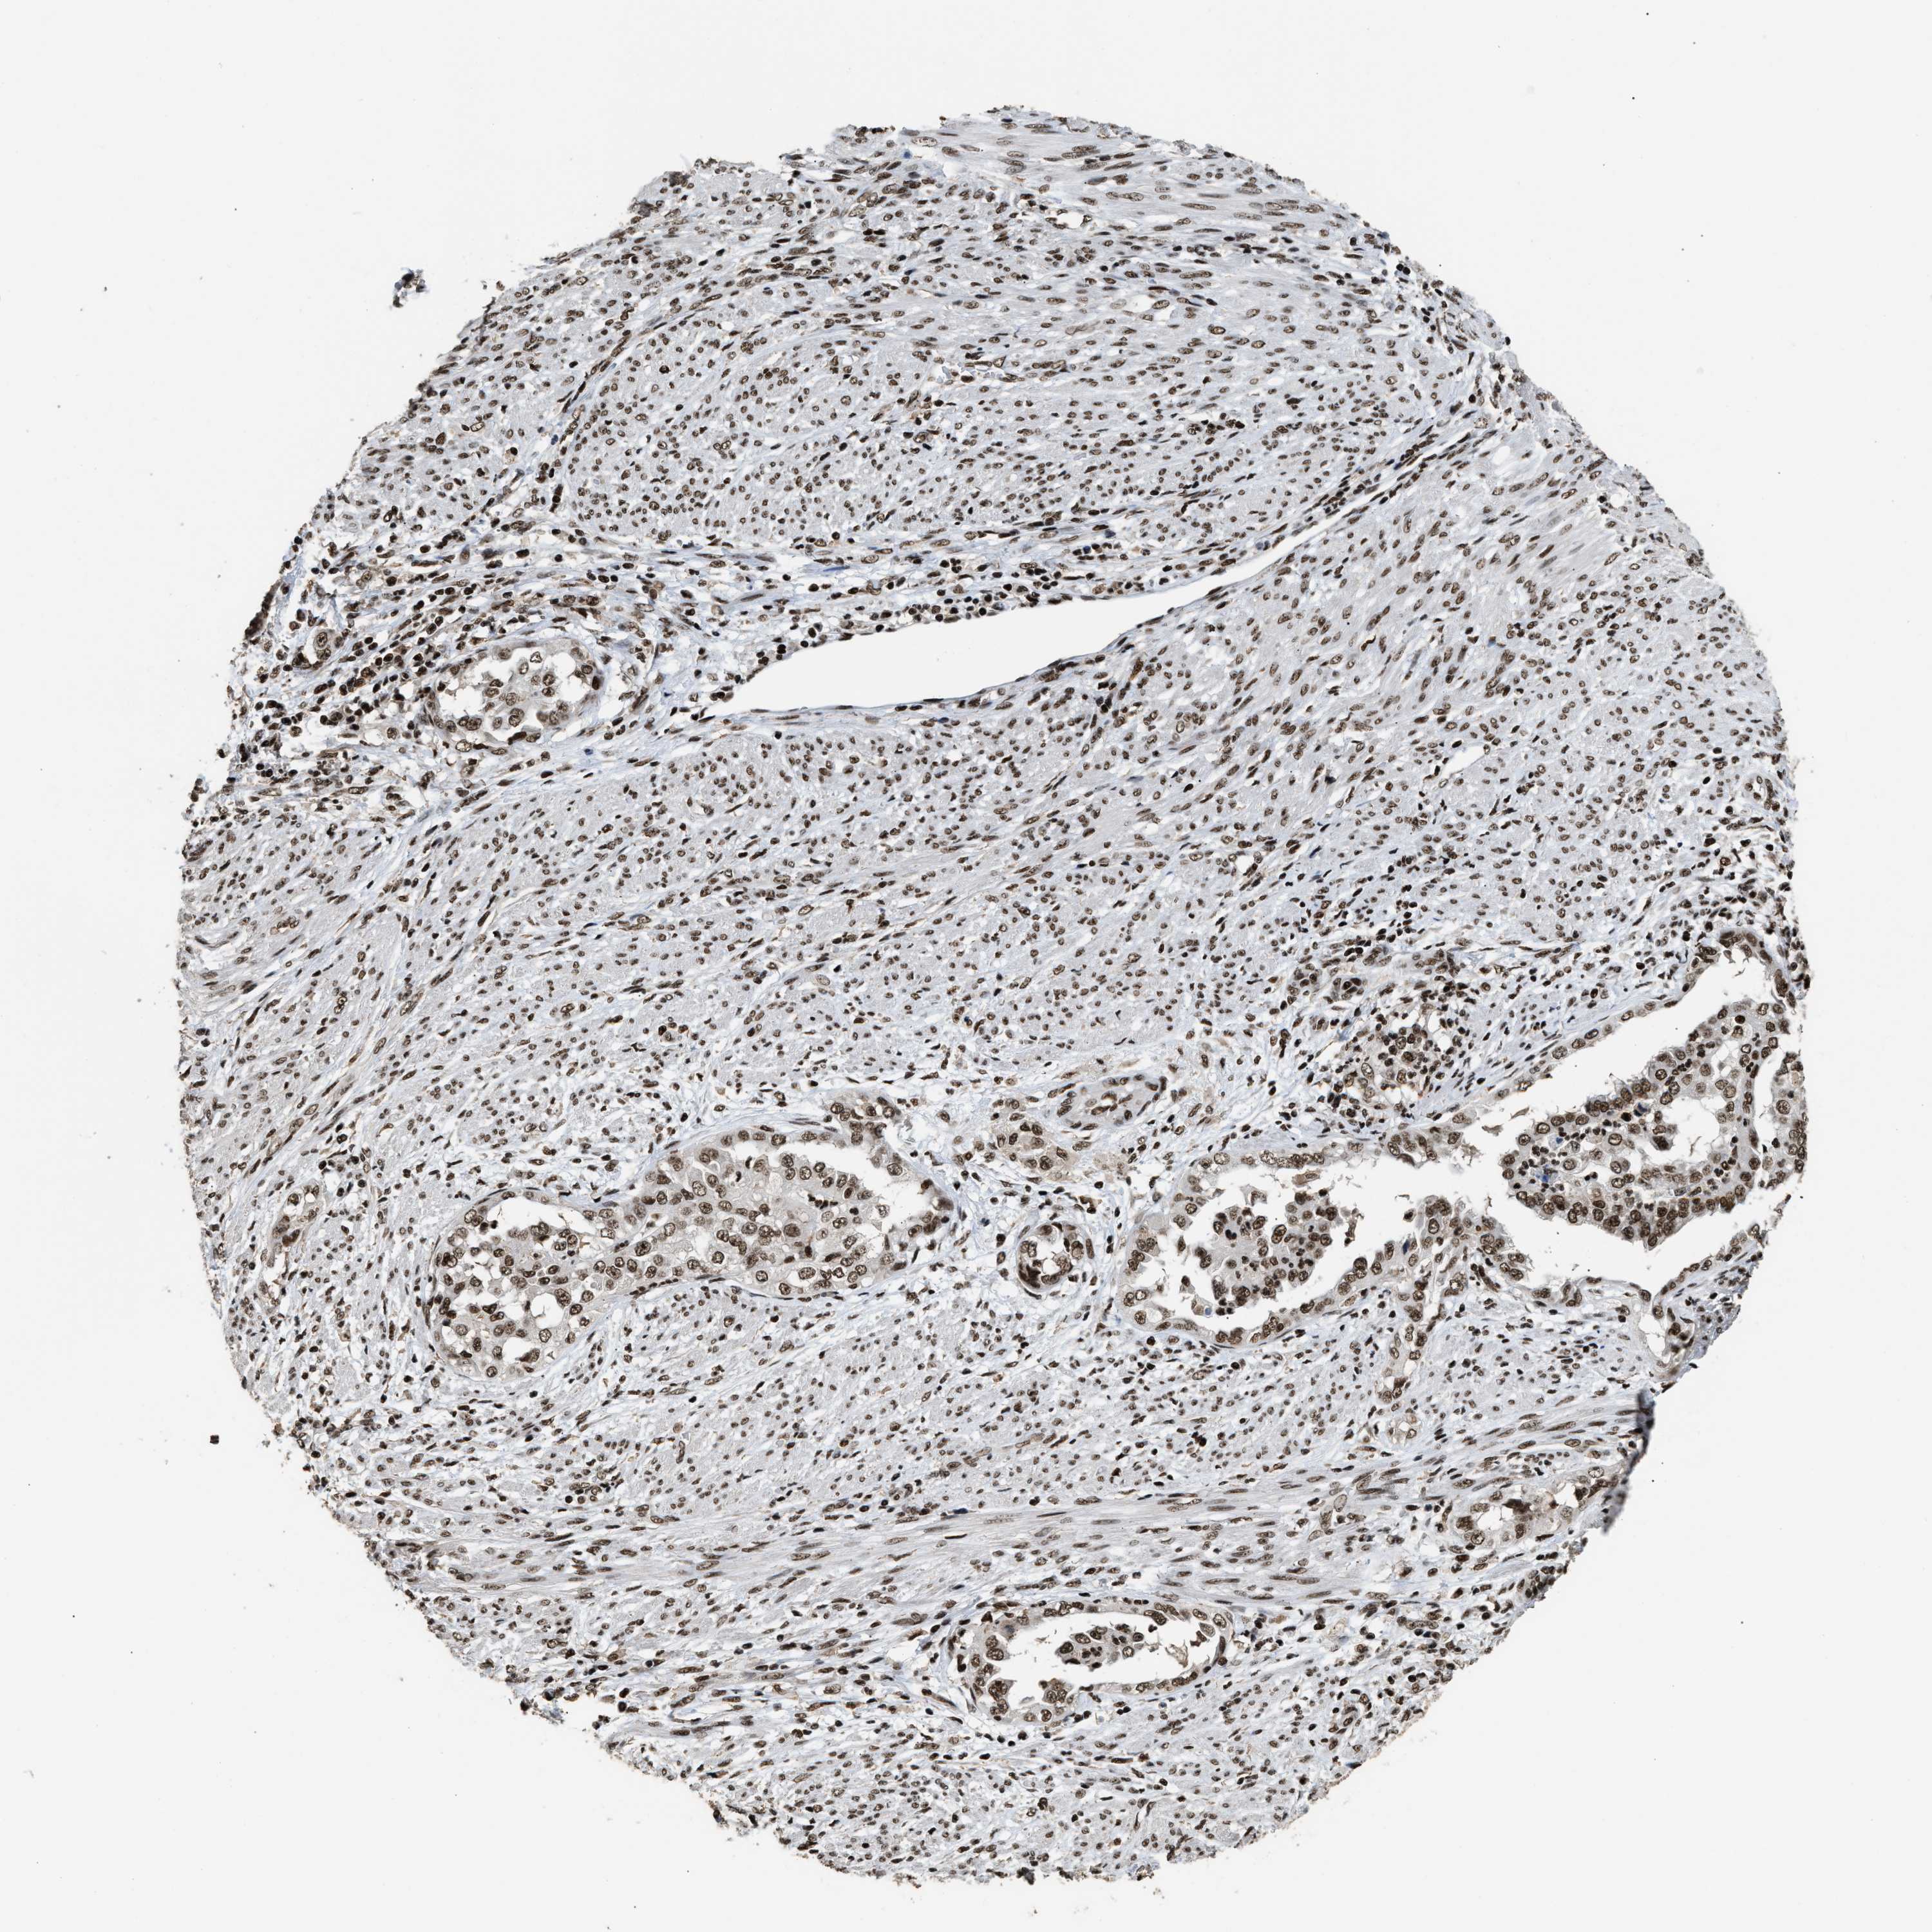

ENDOMETRIAL CANCER - Protein expressioni

A mouse-over function shows sample information and annotation data. Click on an image to view it in a full screen mode. Samples can be filtered based on level of antibody staining by selecting one or several of the following categories: high, medium, low and not detected. The assay and annotation is described here.

Note that samples used for immunohistochemistry by the Human Protein Atlas do not correspond to samples in the TCGA dataset.

Antibody stainingi

Antibody staining in the annotated cell types in the current human tissue is reported as not detected, low, medium, or high, based on conventional immunohistochemistry profiling in selected tissues. This score is based on the combination of the staining intensity and fraction of stained cells.

Each image is clickable and will lead to virtual microscopy that enables deeper exploration of all samples and also displays staining intensity scores, fraction scores and subcellular localization as well as patient and tissue information for each sample.

Antibody HPA020044

Antibody CAB022065

Staining

High

Medium

Low

Not detected

Intensity

Strong

Moderate

Weak

Negative

Quantity

>75%

75%-25%

<25%

None

Location

Nuclear

Cytoplasmic/membranous

Cytoplasmic/membranous,nuclear

Adenocarcinoma, NOS

Adenoma, NOS